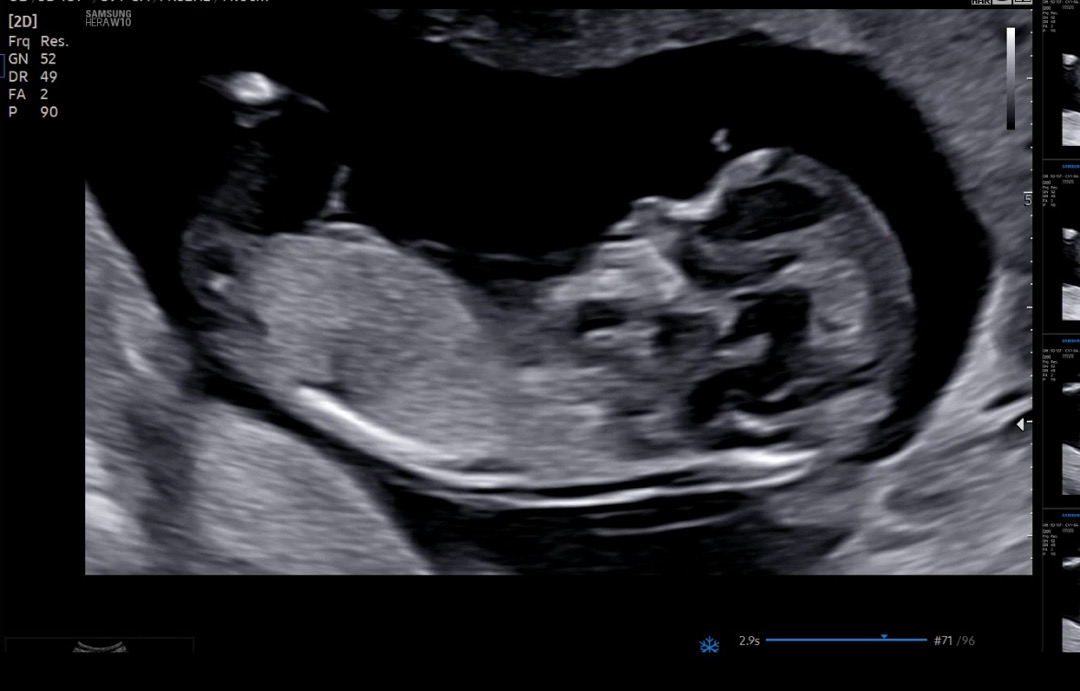

12주6일차 각도법 봐주세용🤍🤍

딸일까용 아들일까용?ㅠㅠㅠㅠ

딸같아요